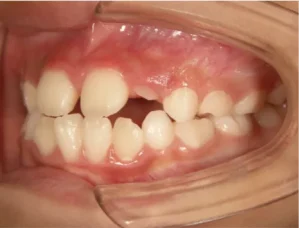

toshi_01_03